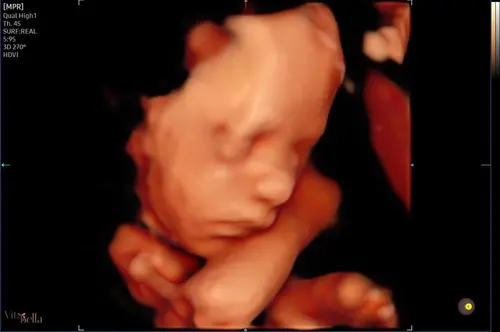

Dit was de echo van ons ventje... al met 22 weken gedaan toen ik in Nederland was. Vandaag 27 weken alweer.